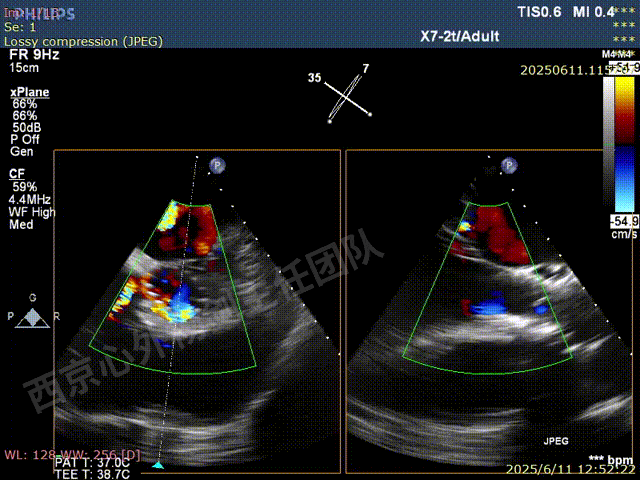

TAVR术后,全心增大,二尖瓣反流重度,三尖瓣反流重度。中量心包积液。左室严重增大,标准图像调整困难。主动脉瓣位带支架人工瓣膜瓣叶启闭正常,主动脉瓣位人工瓣上血流速度Vmax 148cm/s,PGmax 9mmHg,Vmean 86cm/s,PGmean 2mmHg, VTI 34.7cm,瓣周反流(轻)。估测肺动脉收缩压约49mmHg;左室收缩功能明显减低。LVEF:23%,EDV:364ml,ESV:221ml。

彩色血流示:二尖瓣反流缩流颈彩宽6.6mm,面积17cm²,容积30ml;二尖瓣瓣口面积6.6cm²,瓣环内径:左右径34mm,前后径34mm。2区瓣叶长度:前叶36mm,后叶20mm,叶环比1.6. 三尖反流面积17.2cm²,容积33ml,Vmax 291cm/s,PGmax 34mmHg。

二尖瓣后叶栓系严重,前叶相对错位,反流束沿2区分布广泛,2偏3区处存在反流。

反流宽度至少23mm,因影像调整困难,考虑实际反流更宽。